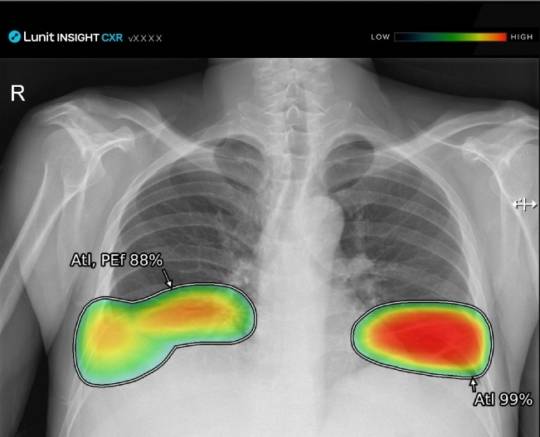

성숙환 이화의료원 이대서울병원 흉부외과 교수는 “폐암을 초기에 발견하기 위해서는 정기적으로 흉부 CT를 촬영하는 것이 필요하다”며 “초기 폐암의 경우 흉부 X선 촬영에서 발견되지 않으나 흉부 CT검사에서는 발견되는 경우가 많다”고 설명했다.

흉부 CT 중 저선량 흉부 CT는 조영제를 사용하지 않고 방사능 피폭을 줄이면서 초기 폐암 진단에 큰 도움이 된다는 게 전문의들의 소견이다.